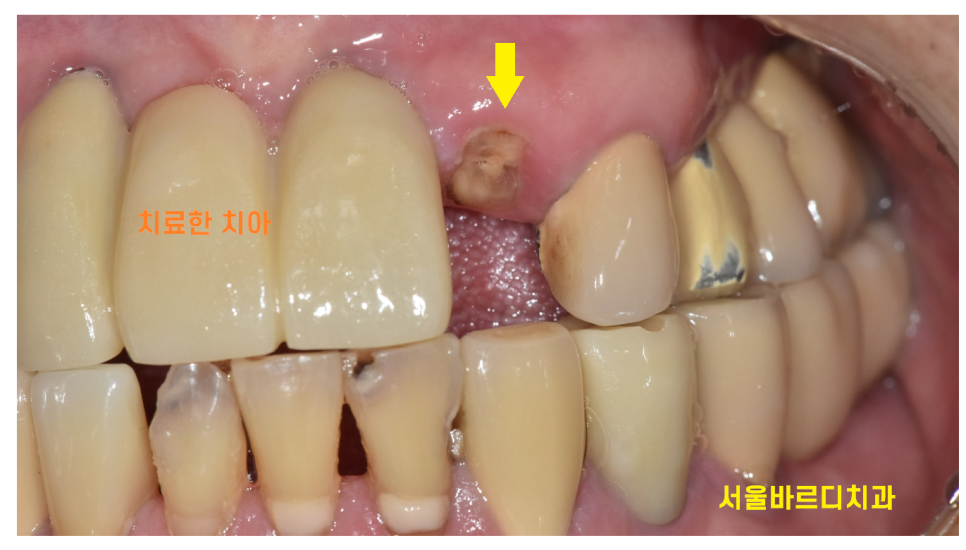

< 완성 사진 >

240312

치료 후 처음에 브릿지 치료로 안한게

참 다행이다 생각이 들었던 것이..

처음 넘어지면서 부러진 앞니 옆 치아에도

충격이 갔었던 모양입니다.

치료를 끝내드리고 6개월정도 지나

옆에 치아가 부러져서

현재 임플란트 치료 진행중입니다.